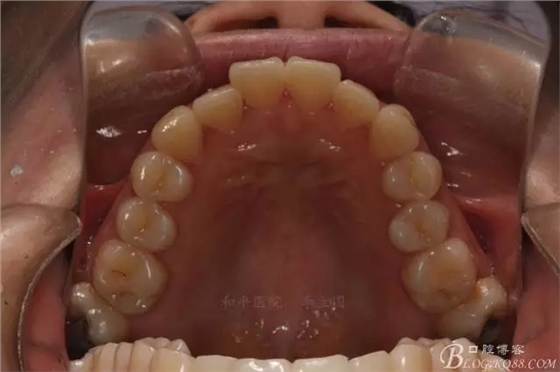

該病例主要為17、27頰側(cè)位同時(shí)伴有伸長(zhǎng),當(dāng)然種植支抗可以解決,但還有簡(jiǎn)單實(shí)用的辦法嗎?如圖,在橫腭桿遠(yuǎn)中延伸出牽引鉤,位置盡量遠(yuǎn)離合平面,7粘舌側(cè)扣,牽引力的方向?yàn)閴旱图吧嘞?,下圖為兩個(gè)月的效果,17已到位,27還未到位。